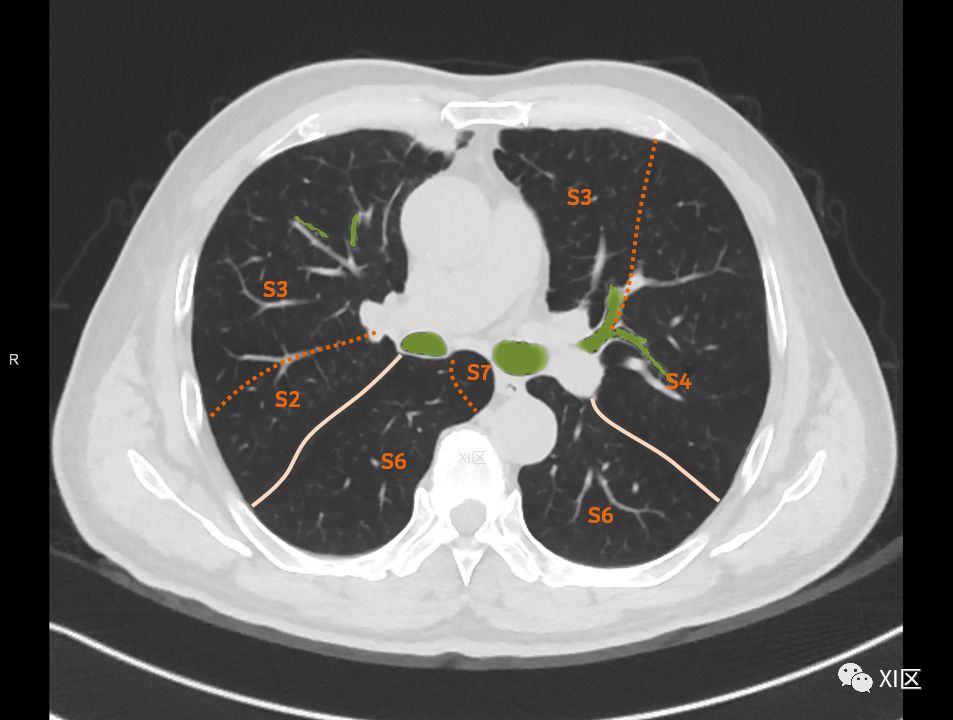

肺的断层分段示意图

在进行肺的分段时,可以上下观察浏览,沿着相应气管的走形可以更容易准确地进行分段。